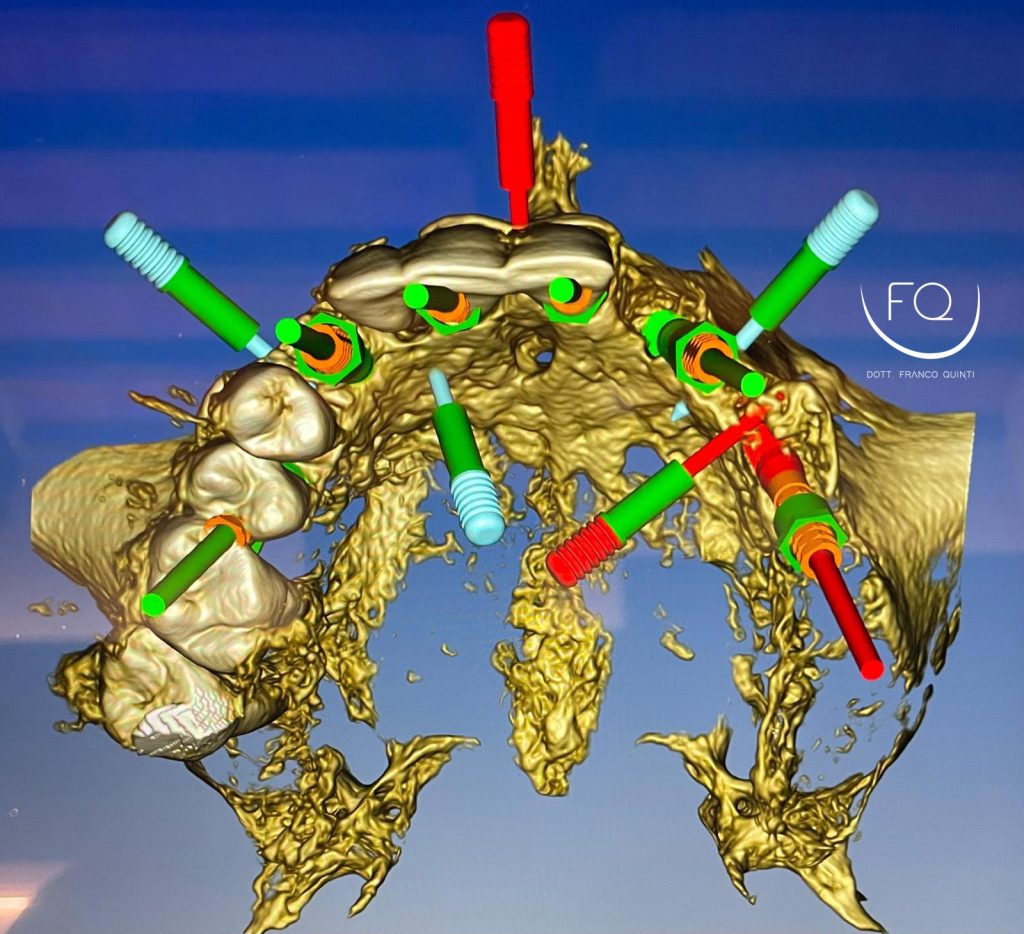

Questa settimana vi presento un caso di chirurgia computer guidata dell’arcata superiore realizzato con dime scomponibili con esecuzione contestuale di un carico immediato.

Nelle prossime settimane vi mostrerò dei brevi video di questo caso relativi alla scomposizione e alla progettazione delle dime chirurgiche.